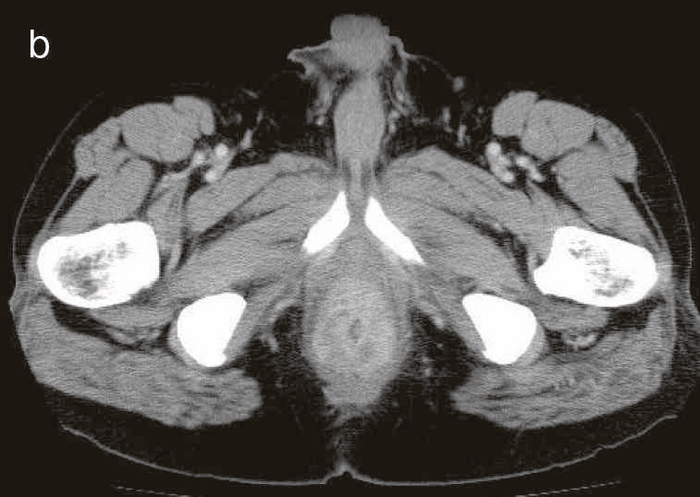

図43 腹部骨盤CT

CTではMRIと同様に広範囲のhigh density areaがあり,癌と炎症が波及した領域の区別がつかず右側方領域にリンパ節腫大を認めた。